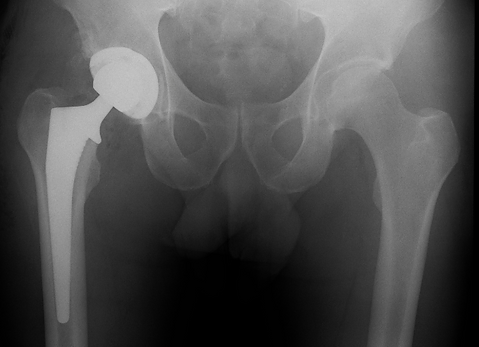

Qu’est-ce qu’une prothèse de hanche ?

Lorsque l’articulation est trop abîmée, on peut la remplacer par une prothèse. C’est comme remplacer une pièce usée dans une machine. La prothèse de hanche est composée de deux parties : une tête en métal ou céramique qui remplace la tête du fémur, montée sur une tige qui prend appui dans le fémur. Et une cupule en métal qui se fixe dans le bassin. Ces pièces sont fixées solidement à vos os. Les deux parties s’articulent ensemble par une pièce intermédiaire en plastique ou céramique, qui permet à la nouvelle hanche de glisser sans effort.

L’opération se fait sous anesthésie générale ou locorégionale (anesthésie du bas du corps). La cicatrice se trouve à l’avant, au niveau de l’aine, ou sur le côté de la fesse. Il faut prévoir entre 1 et 3 jours d’hospitalisation, le temps de surveiller la récupération et apprendre à marcher avec les béquilles.